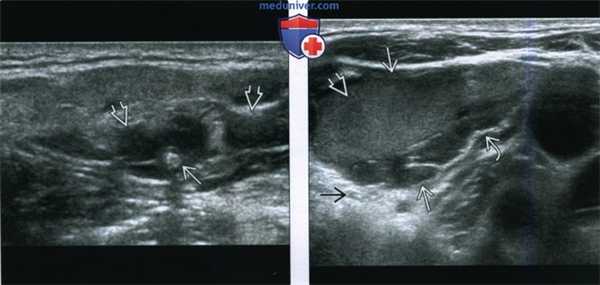

5. УЗИ при венозной мальформации головы и шеи:

• Губчатое, податливое образование

• Мальформации из небольших сосудистых каналов, более эхо-генны и не так подвержены сдавлению, как образования из сосудов с широким просветом

• При цветовой допплерографии артериальный кровоток отсутствует

• При надавливании УЗ-датчиком может наблюдаться усиление венозного кровотока

• Флеболиты = гиперэхогенные очаги с акустической тенью

(Слева) Нa поперечной сонограмме верхних отделов шеи визуализируется кистозное объемное образование смешанной структуры с расширенными синусоидами и эхогенным флеболитом, наличие которого позволяет сделать вывод о венозной мальформации. Тем не менее, УЗИ не позволяет оценить распространенность больших мальформаций в глубокие отделы шеи или подтвердить множественность (из статьи на сайте «Лучевая диагностика: УЗИ»).

(Справа) На поперечной сонограмме у ребенка с безболезненным объемным образованием в нижних отделах шеи визуализируется кистозный очаг с ровными краями: расширенное синусоидальное пространство с небольшими включениями дебриса и перегородками внутри. Обратите внимание на заднее акустическое усиление - признак кистозной природы образования.